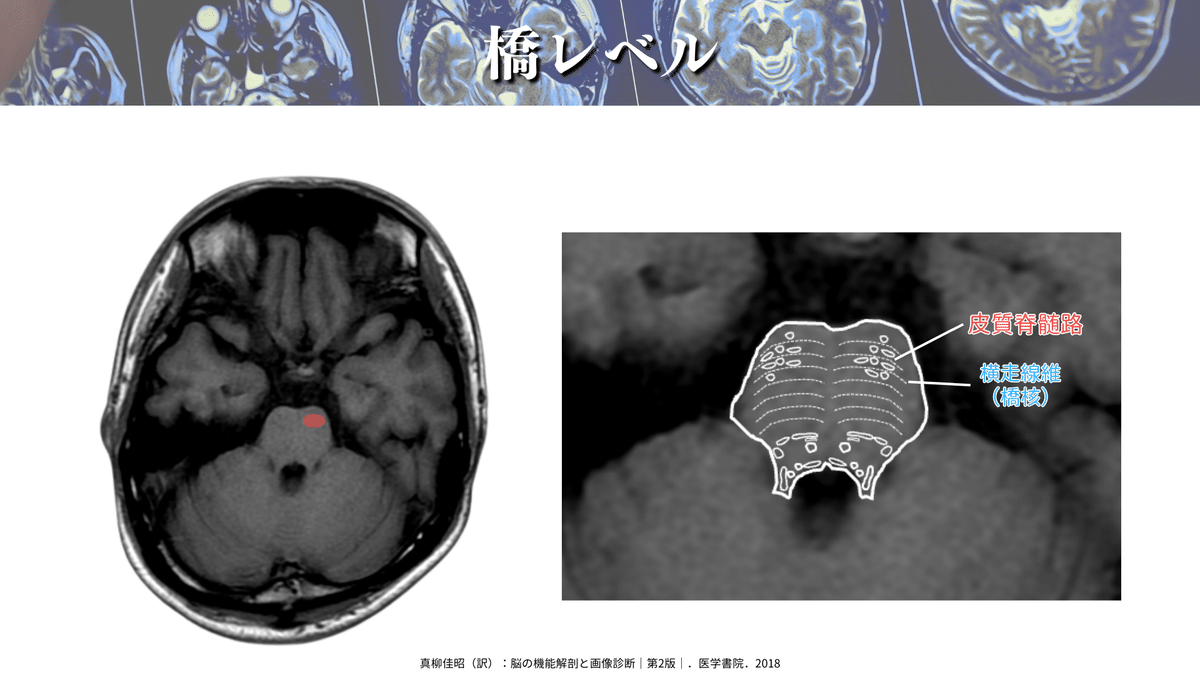

橋レベル

では、さっそく解像度を上げた画像を見てみましょう🔍

CSTは前方(橋底部)を通過しているのが分かりますね👀

橋のレベルは他の脳幹とは少し性質が異なり、右図のようにCSTが分散します!

Q:橋梗塞では運動麻痺が軽度になるってほんと?

右図を見ながら聞いてもらいたいのですが、橋は解剖学的な構造として、内側毛帯を境にして橋底部(腹側)と橋被蓋(背側)に分かれていまして、橋底部をCSTが通過していきます🏃♀️

橋底部は主に橋核から構成されていて、その橋核ニューロンから小脳に向かう横走線維(横橋線維と同義)が大部分を占めています😳

つまり、橋底部は横に走る線維が多く、下降するCSTはその線維を避けて通過しないといけないので、一度CSTは分散する必要があります!(心太みたいなイメージです🎐)

なので、橋ではCSTの密度が薄くなるので、脳梗塞などで損傷をされてもCSTの損傷度合いが小さく済むケースが多く、運動麻痺が軽症になる場合があります✨

このような解剖学的な構造も理解しておくと、臨床に役立つとおもいます💡

橋では主に前方(橋底部)を走行すると覚えるといいかもしれませんね☝️